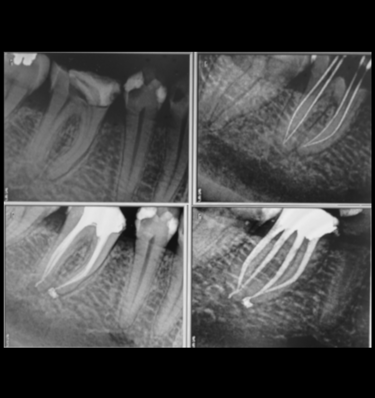

Parodontologie pour l'omnipraticien

Diagnostic et traitement